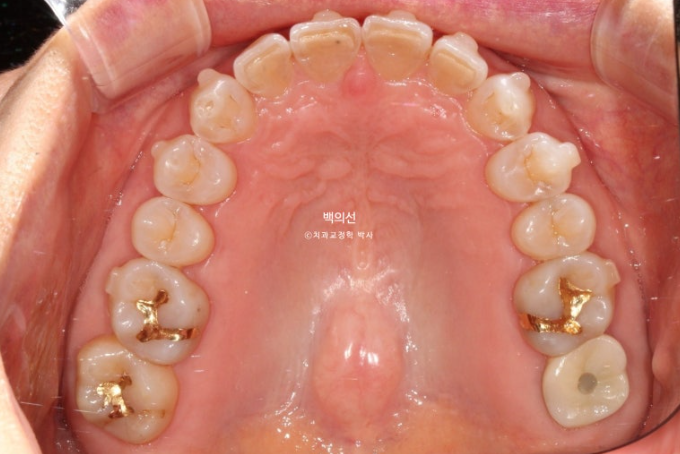

25.02

레진 치료를 감쪽같이 잘 해놓으셨습니다.

앞니의 뻗침이 있습니다.

파란 화살표는 틈을 메워놓은 레진 입니다.

벌어진 틈을 메워놓는 레진을 제거한 모습입니다.

생각보다 틈이 꽤 크죠?